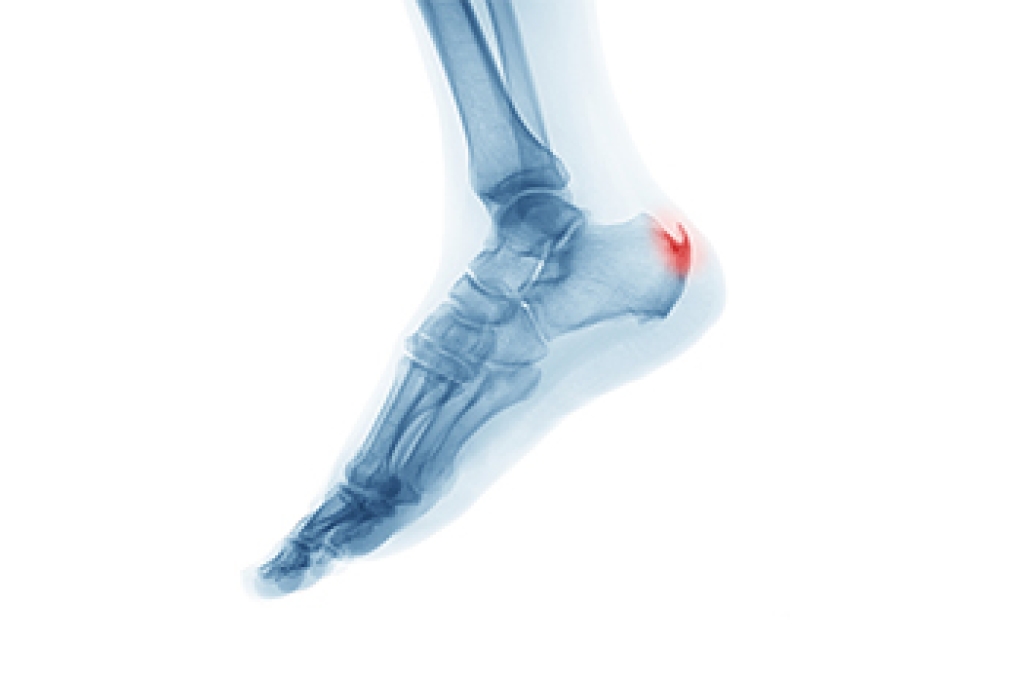

Heel spurs are bony growths that develop on the heel bone, often forming either beneath the heel or at the back where the Achilles tendon attaches. They result from ongoing stress or irritation of the bone, leading to an overproduction of calcium deposits. Over time, this buildup creates a spur-like projection. Several factors can contribute to the formation of a heel spur. Included are tightness in the plantar fascia or calf muscles, repetitive pressure from activities like running or jumping, and irritation from shoes that press against the heel. Foot injuries and chronic conditions like arthritis that cause inflammation, can also play a role. Abnormal foot biomechanics, like flat feet, may increase tension on heel structures, further encouraging bone spur development. Symptoms include sharp pain in the heel when first standing, lingering soreness after activity, stiffness, or the presence of a hard lump. If you have symptoms of a heel spur, it is suggested that you schedule an appointment with a podiatrist for an exam and appropriate treatment.

Heel spurs are formed by calcium deposits on the back of the foot where the heel is. This can also be caused by small fragments of bone breaking off one section of the foot, attaching onto the back of the foot. Heel spurs can also be bone growth on the back of the foot and may grow in the direction of the arch of the foot.